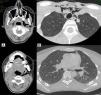

A 22-year-old woman presented in the emergency department with difficulty breathing and swallowing, and pain in the left hemithorax, 2h after two molars were extracted. On physical examination, no changes were seen in the oropharyngeal region, apart from the missing two upper left molars, and no evidence was seen of upper airway compromise. However, crepitation on palpation of the neck and upper chest region were of interest. All vital signs were stable. Computed tomography was performed of the face, cervical spine and chest, revealing pneumomediastinum, involving the upper and anterior mediastinum and subcutaneous emphysema of the neck and face, dissecting even in the deepest cervical planes (Fig. 1). The patient was treated with metamizole and antibiotic prophylaxis with amoxicillin–clavulanic acid. She was discharged 48h later, and attended a follow-up visit in the thoracic surgery department two weeks later, confirming complete resolution of the process.

(A) Subcutaneous emphysema extending to the cervical–facial region, dissecting even in the deepest cervical planes (pterygoid fossa and the submandibular, masticatory, retropharyngeal, parapharyngeal, and left carotid spaces) and (B) pneumomediastinum extending toward the upper (surrounding the trachea, supraaortic trunks, and adjacent structures) and anterior (in front of the pericardium and the outlets of the great vessels).